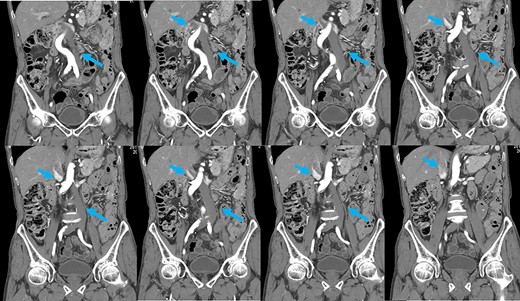

Preoperative computed tomography (CT) revealed a tumor in the sigmoid colon accompanied by some regional lymph node swelling (Fig. 1). It also showed that the IVC ascended vertically along the left side of the abdominal aorta. After connecting with the left renal veins, the left-sided IVC crossed the abdominal aorta anteriorly to join the normal prehepatic segment of the IVC (Figs 2 and 3). Coronal CT showed that the descending colon misplaced at the abdominal midline and the sigmoid colon in the right upper abdomen (Fig. 4). The preoperative diagnosis was thus sigmoid colon cancer with left-sided IVC and PDM.

Coronal reformation of the CT image shows precisely how the left-sided IVC (arrows) ascended vertically along the left side of the abdominal aorta and crossed anterior to the aorta.

PDM is a developmental anomaly characterized by failure of the descending mesocolon mesentery to fuse with the posterolateral parietal peritoneum [2]. The non-fused mesentery is then responsible for considerable variations in the position of the descending mesocolon. In our case, the descending colon was at the abdominal midline, and the sigmoid colon was in the right upper abdomen. Coronal reformatted images obtained by multidetector CT (MDCT) proved useful for an accurate preoperative diagnosis of the malpositioned descending colon. It is widely accepted that MDCT is an effective technique for staging colon cancer preoperatively [10]. MDCT also allowed us to generate multiplanar coronal images, which depicted the location of the colon as it would appear during the surgery. Moreover, MDCT angiography can be used to evaluate the running direction of the vessels. Because it has been reported that the left colon and sigmoid colon arteries and the superior rectal artery often branch radially from the inferior mesenteric artery, and that a marginal vessel may run abnormally due to the unusual mesenteric adhesion [5], accurate evaluation of the arteries is important for safe lymph node dissection.